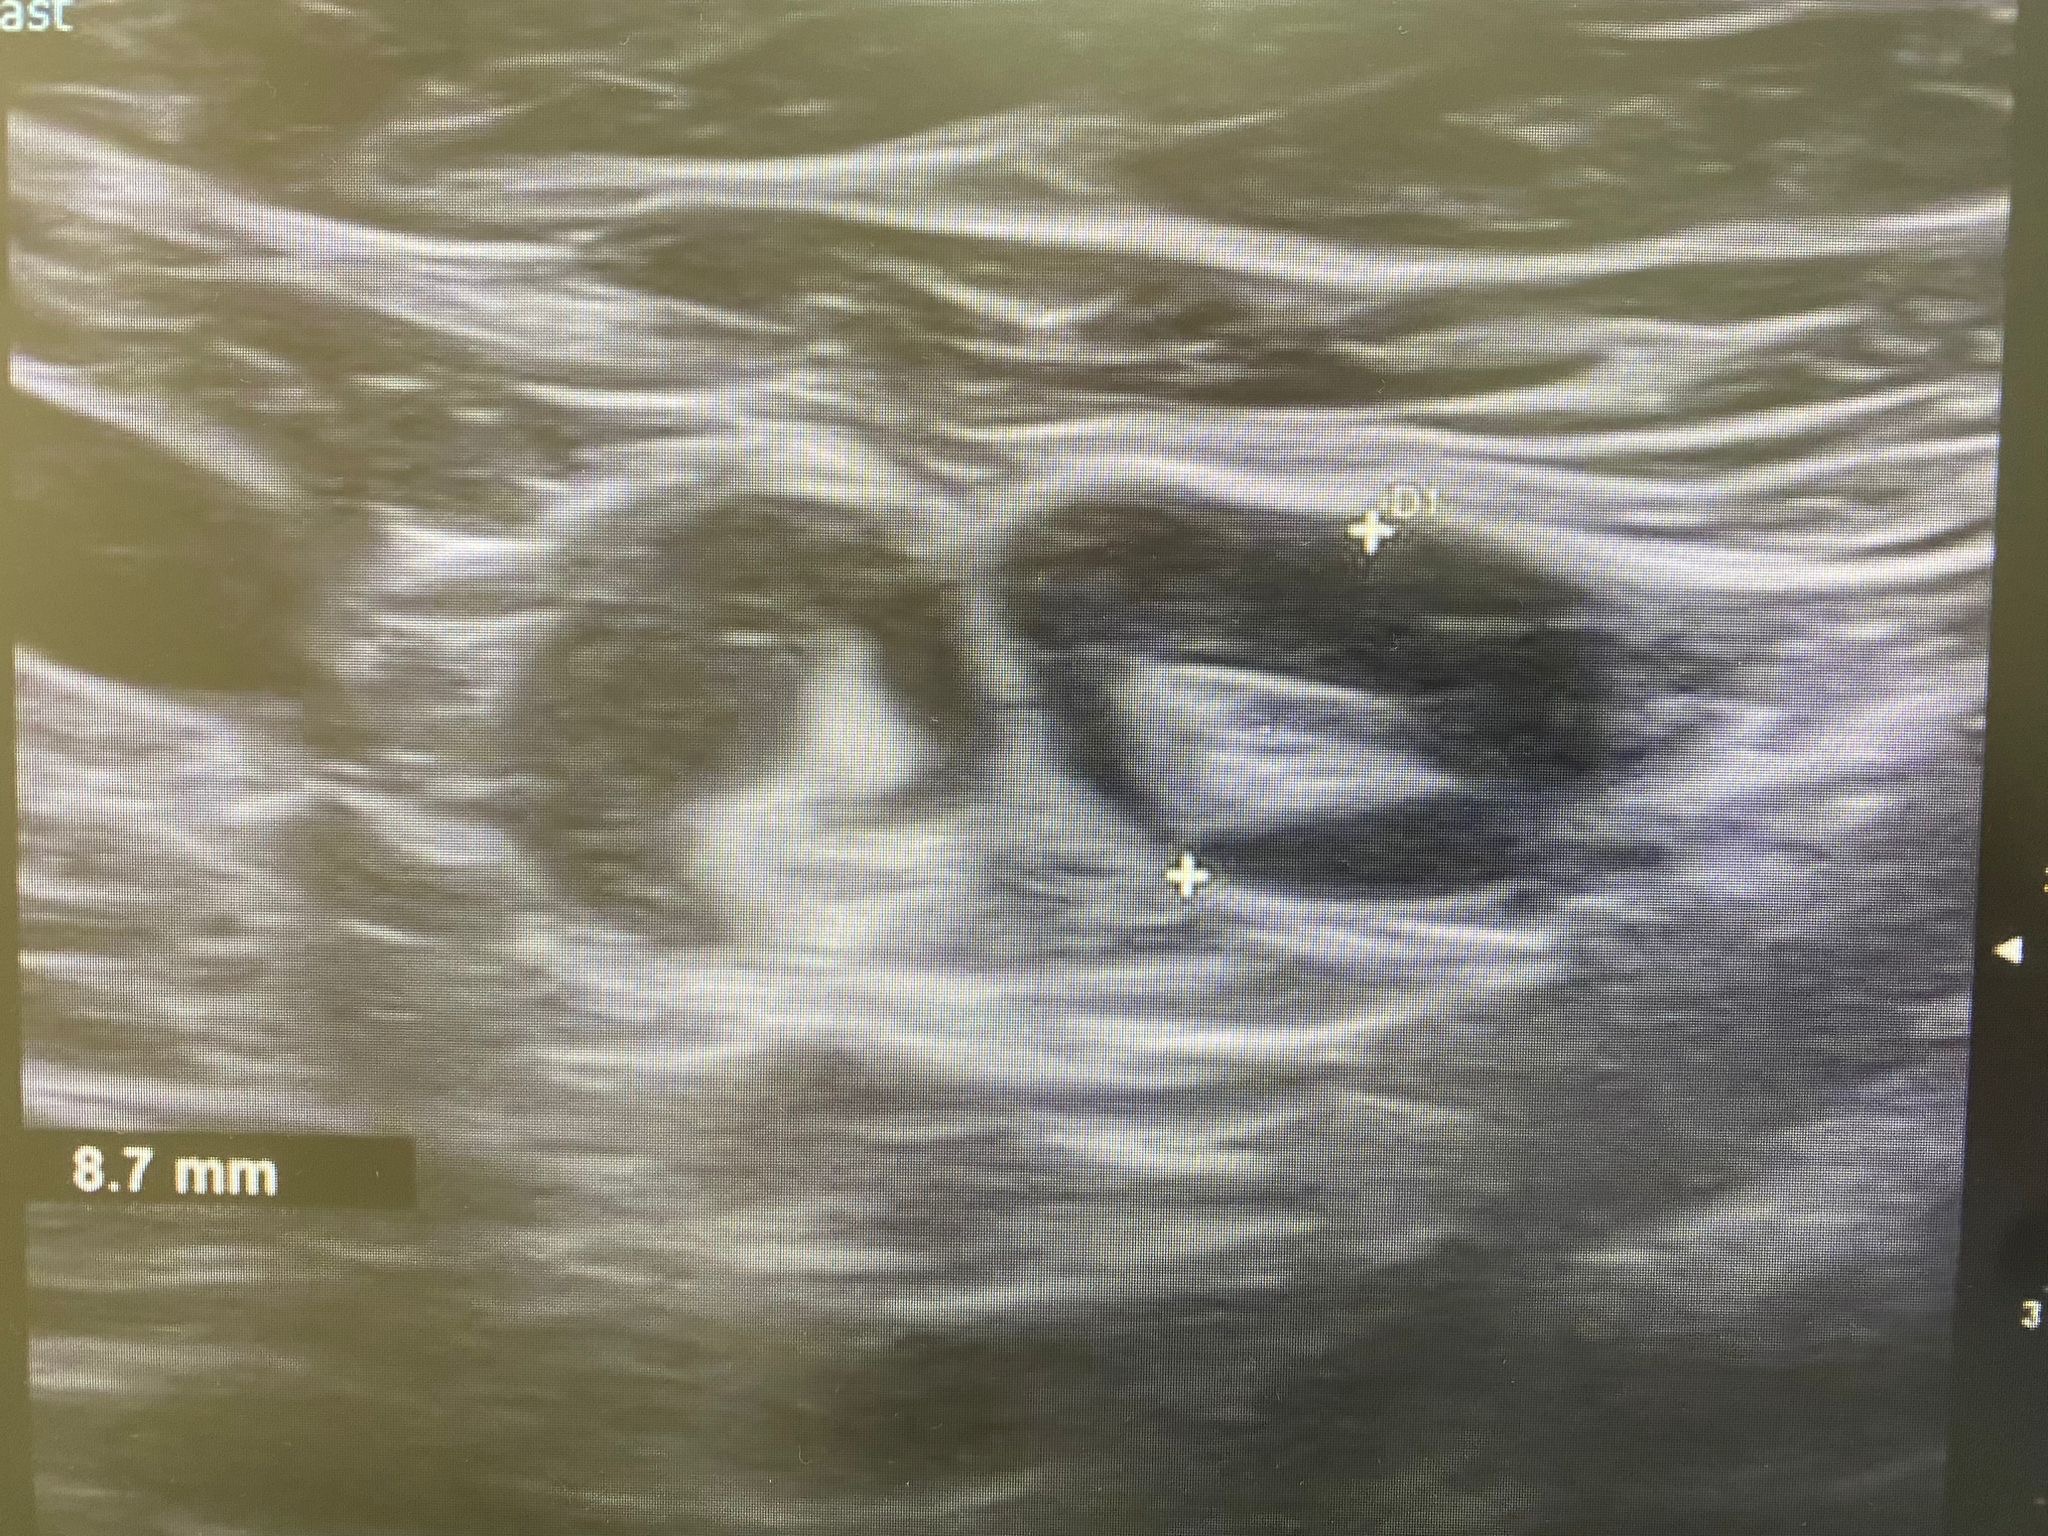

Ecografía: Valoración de adenopatías para acercamiento diagnóstico (típicas/atípicas).

Hallazgos ecográficos

Adenopatías patológicas, algunas redondeadas, con eje anteroposterior > 1 cm, parénquima homogéneo, cortical engrosada aunque con hilio respetado.

Ecografía mamas: quistes y nódulos hipoecogénicos bilaterales.

Ecografía axilar: múltiples adenopatías con eje corto > 2 cm y cortical engrosada.